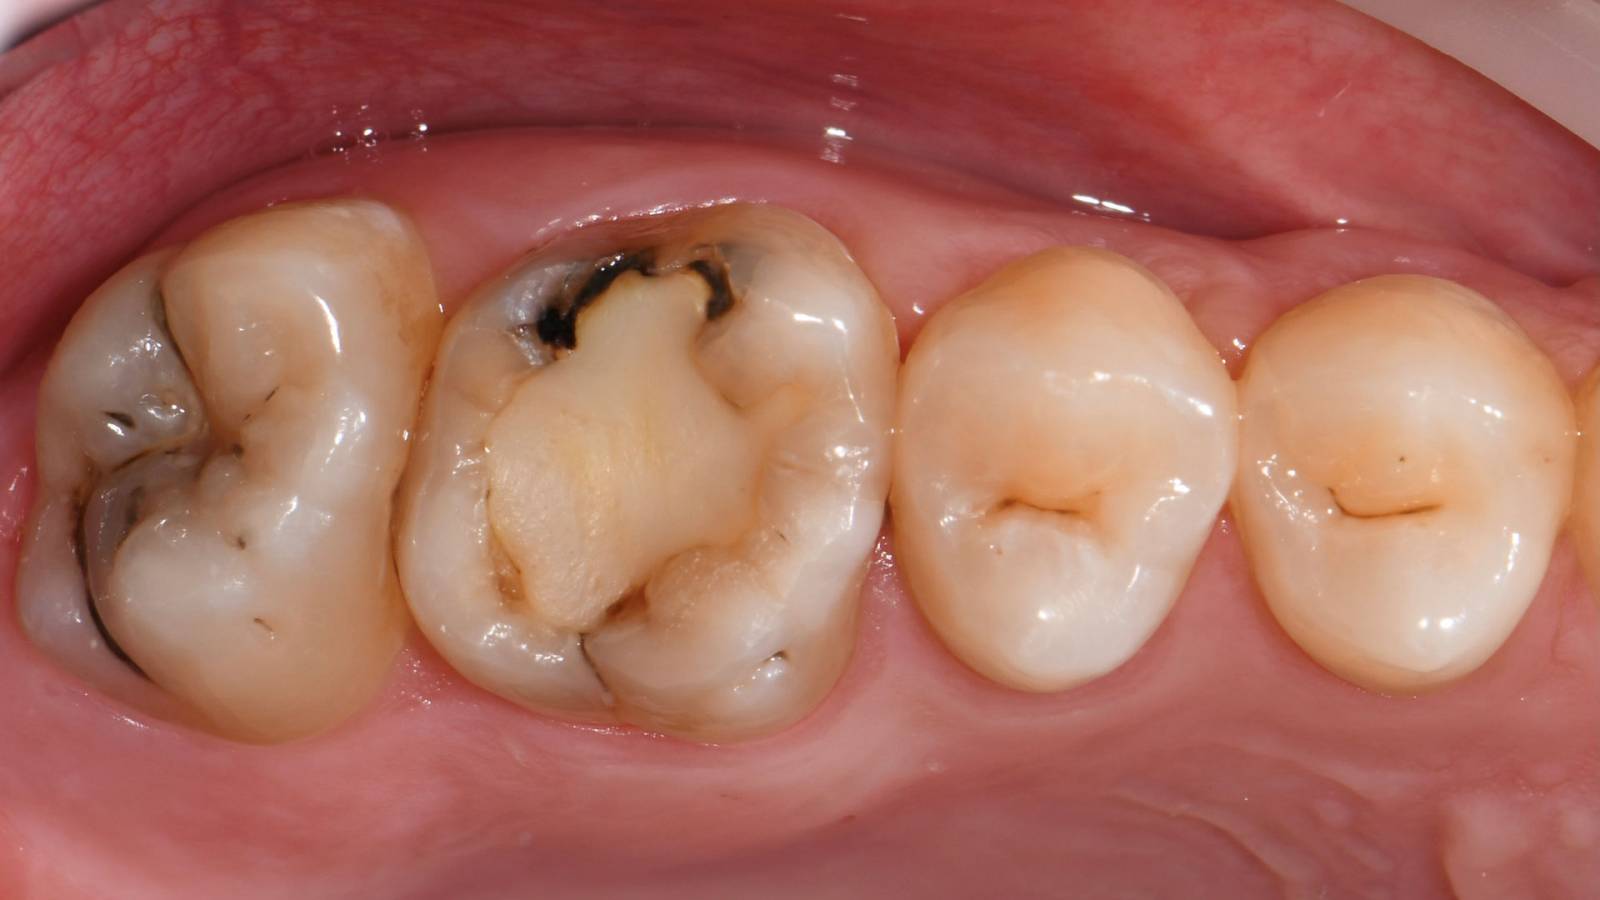

First upper molar, in 60 minutes

IPS e.max CAD single crown

The clinical case demonstrates how quickly and efficiently CEREC Primemill allows a full-surface glass-ceramic crown to be fabricated chairside in a single session, while meeting the highest esthetic demands.

Before: Large insufficiency of the composite filling on tooth 16 with distal marginal ridge cracks, a lingual wall crack and distal recurrent decay.

After: Highly esthetic full-surface glass-ceramic crown.

Dr. Karyn M. Halpern DMD, MS

New York, USA